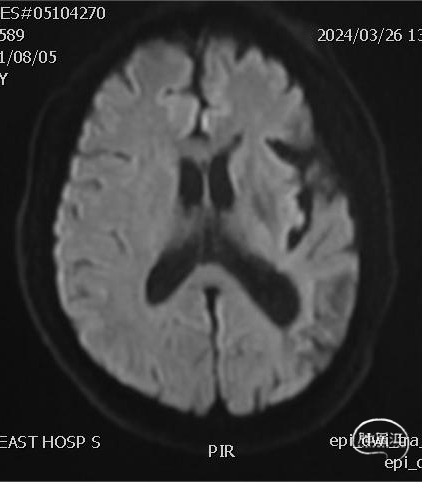

➢ 头颅MRI

左侧顶枕叶陈旧性梗塞,未见新发梗塞病灶。